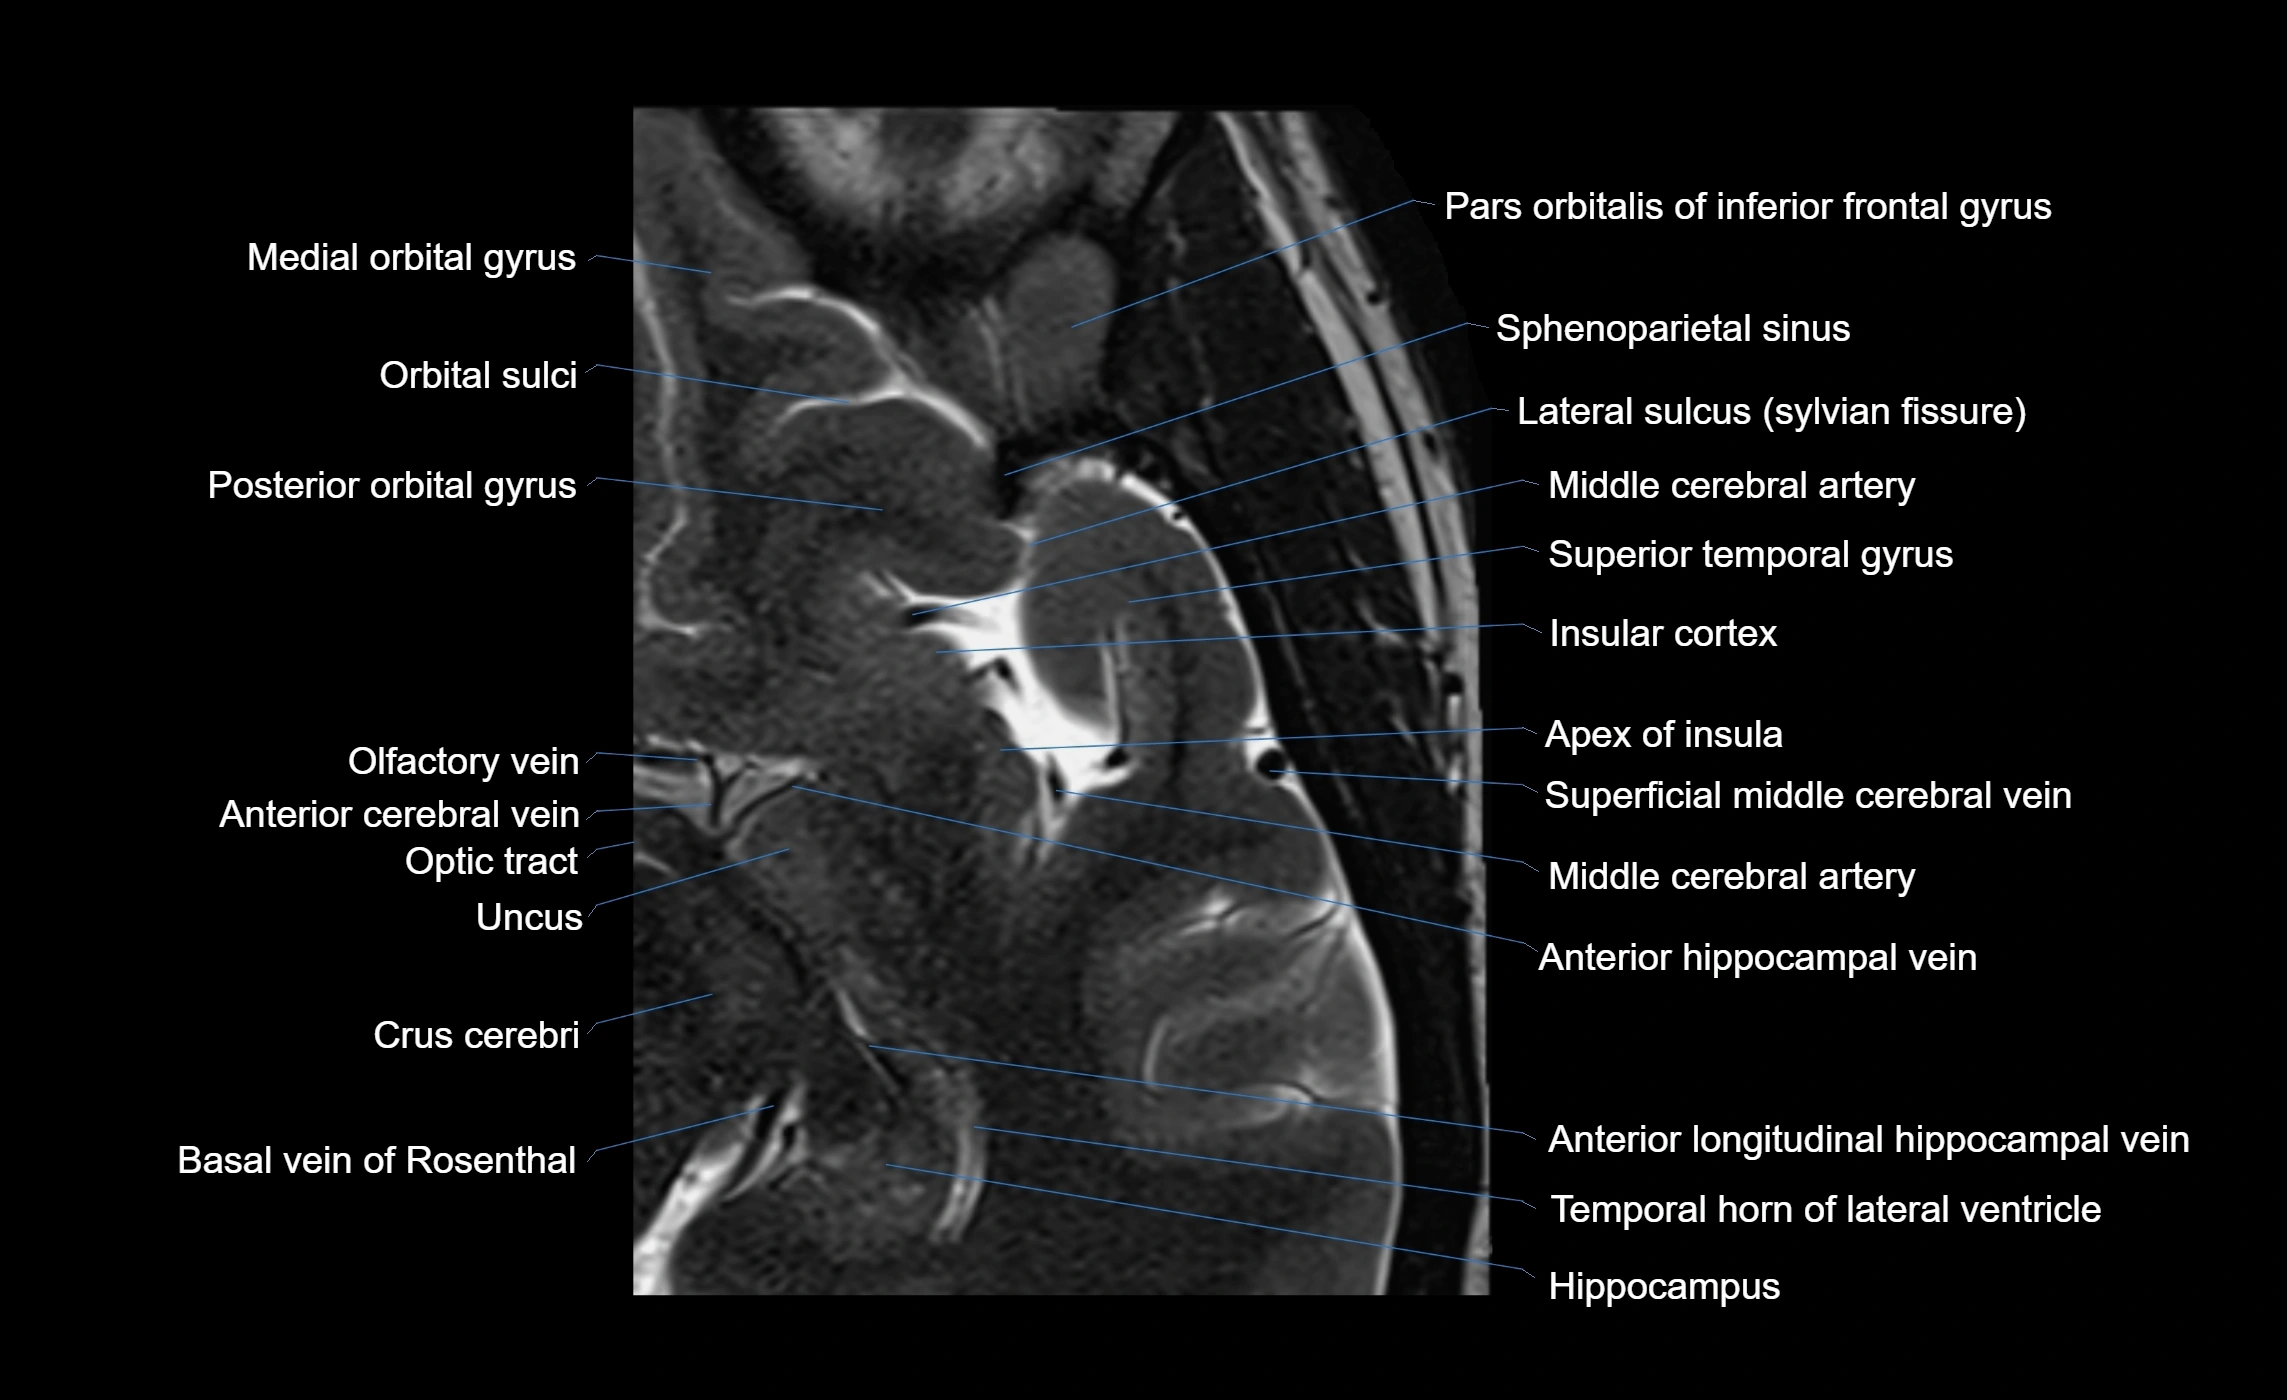

The anterior ascending ramus of the Sylvian fissure is a significant anatomical landmark in the lateral surface of the cerebral hemisphere. It represents one of the key branches of the Sylvian fissure (also known as the lateral sulcus) and plays an essential role in demarcating the boundaries between important cortical regions, notably within the frontal and parietal lobes. Understanding its anatomy and imaging appearance is crucial in neuroradiology, neurosurgery, and neuroanatomy for accurate localization and identification of adjacent brain structures.

• The anterior ascending ramus is a short, superiorly oriented branch that arises from the main stem of the Sylvian fissure.

• It projects upward (anteriorly and slightly dorsally) from the lateral sulcus into the inferior frontal gyrus.

• This ramus separates the pars opercularis (opercular part) from the pars triangularis (triangular part) of the inferior frontal gyrus.

• The anterior ascending ramus marks the boundary between Broca's area and adjacent cortical areas in the dominant hemisphere.

• Supplied predominantly by branches of the middle cerebral artery (MCA), particularly its opercular branches.

• The MCA runs within the Sylvian fissure and provides small cortical branches to adjacent gyri and sulci.

• Drained by superficial Sylvian veins (also called superficial middle cerebral veins), which follow the course of the Sylvian fissure.

• Venous blood ultimately drains into the sphenoparietal sinus and cavernous sinus.

MRI Appearance

• T1-weighted imaging:

• The Sylvian fissure and its anterior ascending ramus appear as low-signal intensity (dark) CSF-filled clefts between the gyri.

• Clear demarcation between adjacent gray and white matter.

• T2-weighted imaging:

• The fissure, including the anterior ascending ramus, is hyperintense (bright) due to CSF signal.

• Better visualization of the separation between opercular and triangular parts of the inferior frontal gyrus.